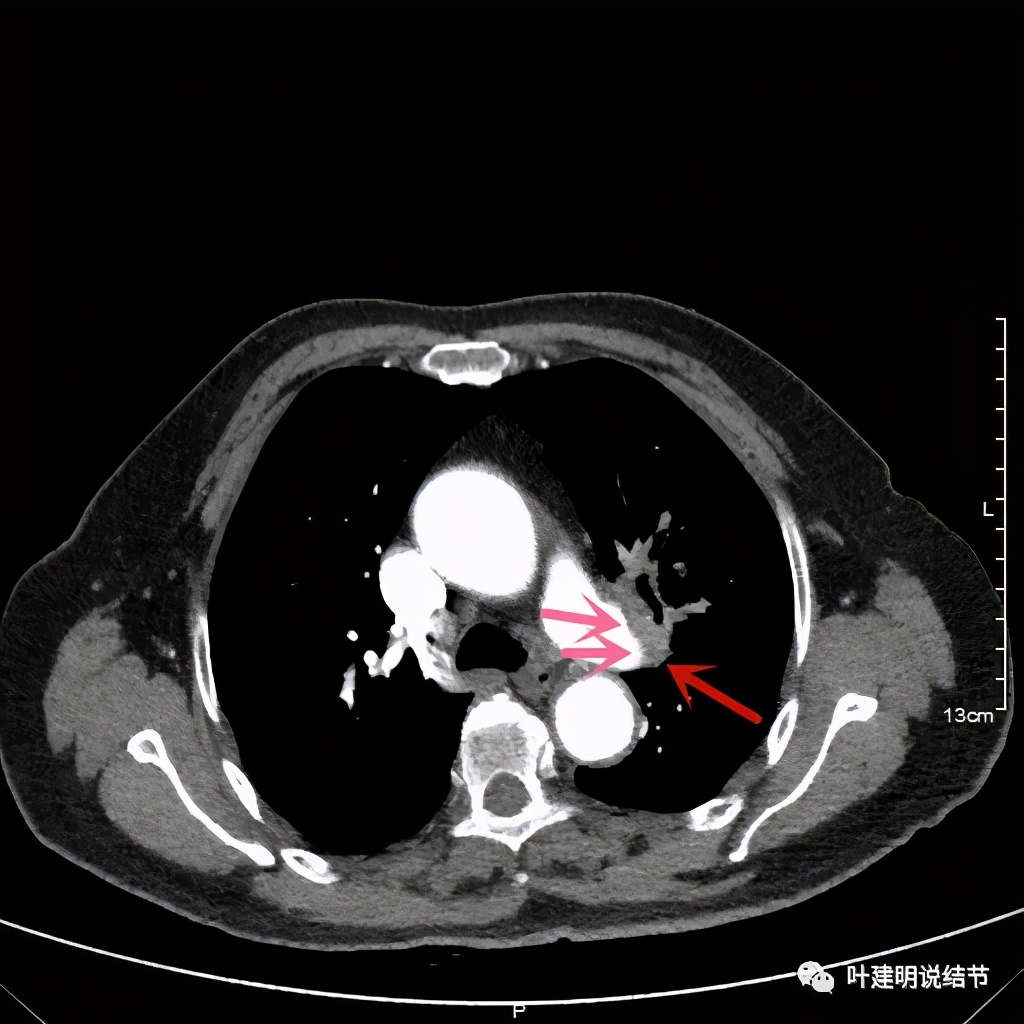

上图桔色箭头示左肺动脉分支处仍被软组织(原肿瘤所在)包绕,粉色箭头示肺动脉仍与肿瘤处关系密切

上图也示桔色箭头示左肺动脉分支处仍被软组织(原肿瘤所在)包绕,粉色箭头示肺动脉仍与肿瘤处关系密切